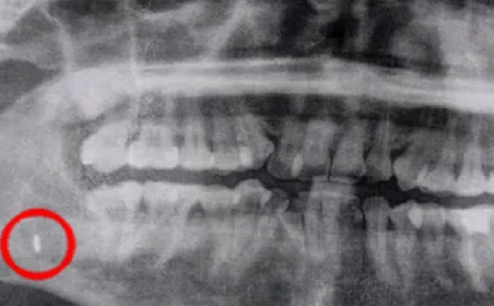

33 yaşlı Krittik Rittixanın 5 il əvvəl dişini çəkiblər. Əməliyyat zamanı alətin iti ucu sınır və qızın çənə sümüyündə qalır. Həkimlər bildirilər ki, yara sağalanda dəmir özü çölə çıxacaq. Amma bundan sonra qız çənəsinin aşağı hissəsi və dilinin keyiməsindən şikayət etməyə başlayır. Bu ilin əvvəlində Rittixan mütəxəssislərə müraciət edir və məlum olur ki, alətin ucu hələ də onun çənəsindədir. Bu isə infeksiyaya səbəb olub. Stomatoloqlar əməliyyat etmək barədə qərara gəlirlər. Əməliyyat nəticəsində alətin ucu qızın çənəsindən çıxarılır.

7News.Az "Ölkə.Az"a istinadən xəbər verir ki, həkimlər qızın ağzının çənə sümüyündən 5 il əvvəl unudulmuş cərrahiyyə alətinin iti ucunu çıxarıblar. Bu barədə "Asia One" nəşri xəbər yazıb.